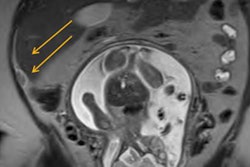

Ultrasound, CT, and MRI are all viable supplemental imaging modalities for assessing acute appendicitis after initial ultrasound, according to a study published online June 19 in Radiology.

The team led by Dr. Kevin Eng conducted a literature search on Medline and Embase, identifying studies that used surgery or histopathologic exam information alone or in combination with clinical follow-up or chart review to assess the diagnostic accuracy of supplemental imaging modalities for appendicitis.

All three modalities had comparable, high accuracy for diagnosing the disease, both in children and adults, the researchers found.

"All three modalities may be valid as second-line imaging in a clinical imaging pathway for diagnosis and management of appendicitis," they concluded.